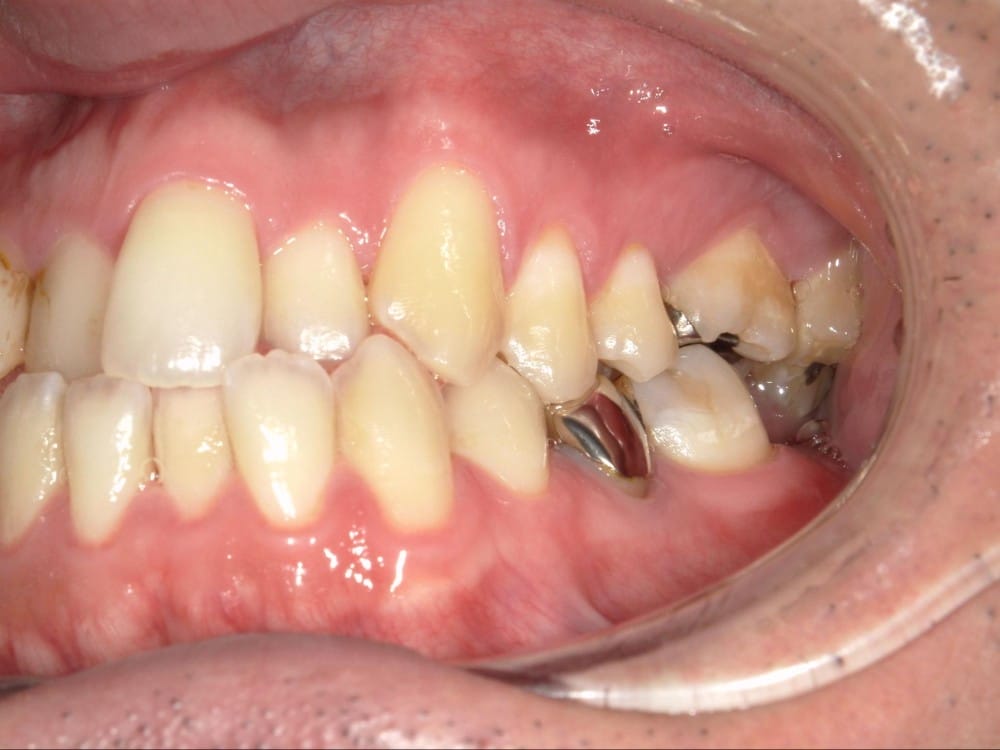

このような奥歯の移動量が大きい症例では、マウスピースだけでは難しいことがあり、カリエールとよばれる装置を補助的に使用し、上下の噛み合わせの前後関係を整えることで、手術を行わずに機能面と見た目の両方が改善することがあります。

一時的に前歯は噛み合わせが開いていますが、受け口の矯正では、最終段階で前歯ばっかりあたって奥歯がしっかり噛まないということも起こりやすいので、あえて狙って動かしています。

ここから上下透明なマウスピースに変え、仕上げていきました。